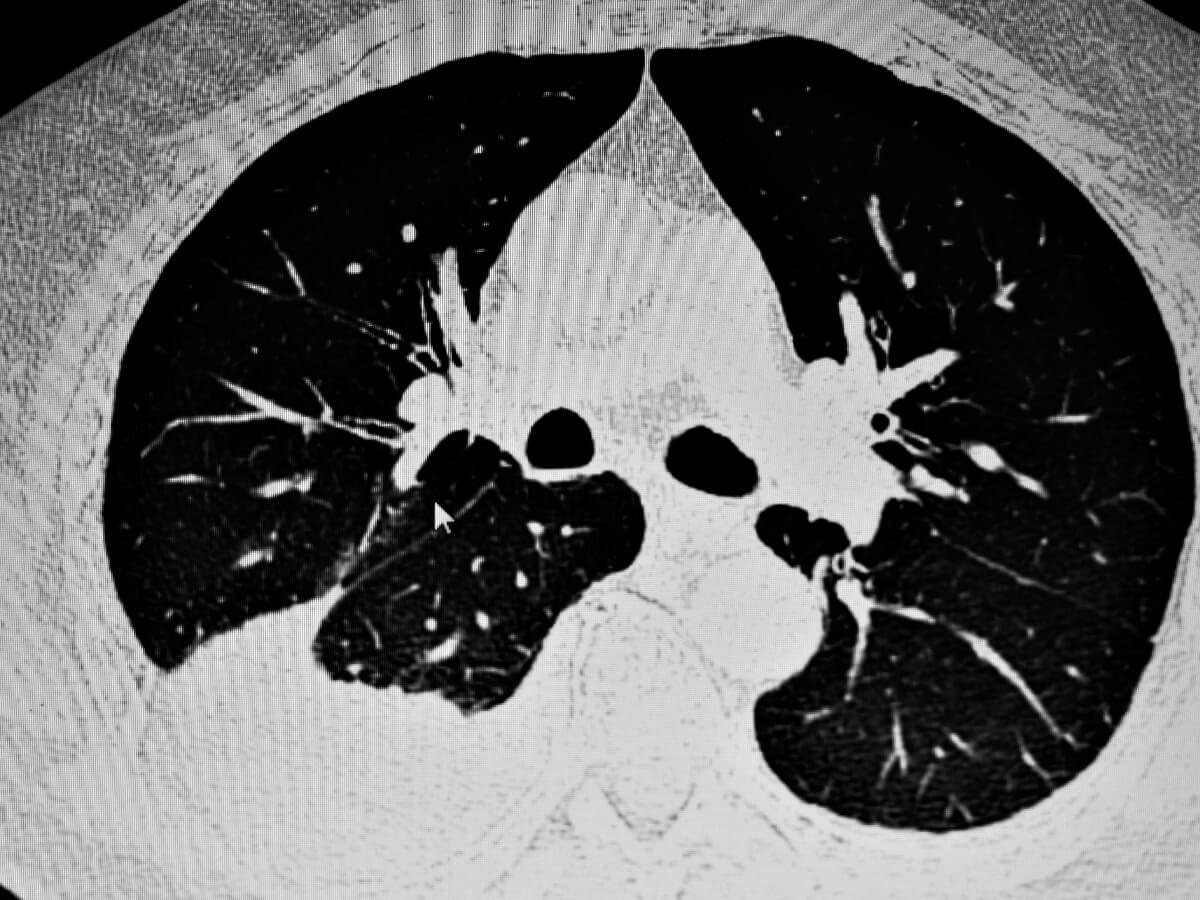

Wenn der Verdacht auf ein Atemwegsproblem besteht, werden in der Regel Röntgenaufnahmen gemacht, um den Gesundheitszustand des Tieres direkt zu beobachten. Ultraschalluntersuchungen können hilfreich sein, insbesondere wenn die Flüssigkeitsansammlung in der Pleurahöhle sehr gering ist.